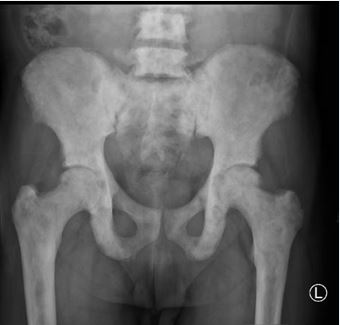

https://www.jscimedcentral.com/public/assets/images/uploads/image-1768992429-1.JPG

Figure 3 Osteoblastic lesions; X ray image showing diffuse osteoblastic lesions involving the pelvis and proximal femur in a patient with prostate carcinoma attending at our center

Radiologically, 59.7% of the metastatic bone lesions were osteoblastic/sclerotic (Figure 3) while 23.6% were osteolytic and 16.7% had mixed sclerotic and lytic lesions. These findings are contrary to most of the studies we reviewed where osteolytic lesions were more common than osteoblastic lesions [20-25]. This might be explained by the fact that in their studies the commonest primary

cancers are breast and lung malignancy while in our study the commonest primary is prostate carcinoma. Breast and lung cancer have been shown to form more lytic bone lesions than osteoblastic while prostate carcinoma forms more osteoblastic bone lesions.